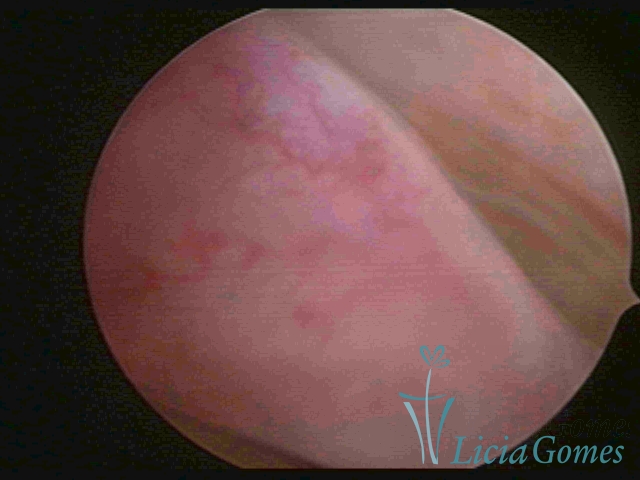

PÓLIPOS ENDOCERVICAIS

São tumores benignos, resultantes da proliferação focal reativa aos processos inflamatórios ou à situações de hiperestrogenismo, e podem ter sésseis (com a base de implantação larga) ou pediculados do epitélio.